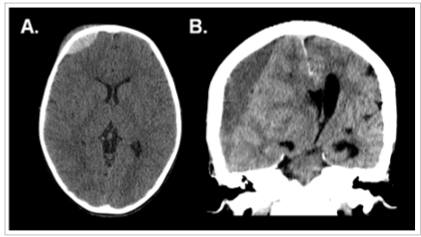

As imagens a seguir referem-se a dois pacientes diferentes, previamente hígidos, com traumatismo cranioencefálico.

Em relação às características das lesões intracranianas evidenciadas tem-se que: